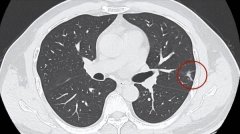

• 基因突变?男子家族里9口人患癌症8人离世!

秦先生 肺癌 患癌 2025/03/07